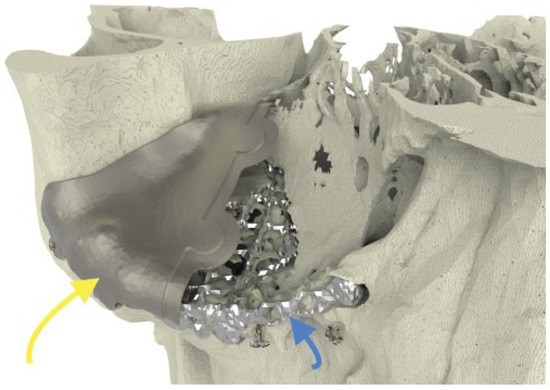

A 28-year-old man was referred with disabling diplopia and severe globe malposition after two repairs of an impure orbital floor fracture using a stock titanium orbital mesh plate (►Figure 9). He had been hit by a pulley in a work accident. The presence of the previously inserted titanium mesh slightly hindered implant design because of the scatter effect on CT scan. Mirroring revealed a height difference of 7 mm between the unaffected side and the mesh on the affected side (►Figure 10, Figure 11 and Figure 12). The 3D model had to take into account the lower position of the orbital rim, and the screw position was based on the amount of remaining bone and positions of the mesh, infraorbital canal, and lacrimal system. The porous implants were printed with a double tongue-in-groove design (►Figure 1 and Figure 10). The puzzle-piece design allowed precise fit between the first and second implants (►Figure 12). Anterior flanges were not necessary as the shape of the reconstructed infraorbital rim provided anteroposterior guidance. Slight diplopia in extreme upward gaze and lagophthalmos remained because of previous fibrosis (►Figure 9).

Figure 10. Case 3: The long yellow arrow indicates the lateral implant. The small blue arrow indicates the previously inserted titanium mesh.

Figure 12. Case 3: Intraoperative 3D imaging using the Pulsera fluoroscopy system. (a) 3D reconstruction and section plane indication. (b) Good fit of the two puzzle pieces (long yellow arrow). Malpositioned mesh (short blue arrow). (c) Good fit of the medial puzzle-piece (long yellow arrow). The titanium mesh was not prebent and was 7 mm too low at the posterior sigmoid bulge (short blue arrow). (d) Axial view of the titanium mesh. The two-piece puzzle implants are visible only where they overlap the infraorbital rim.